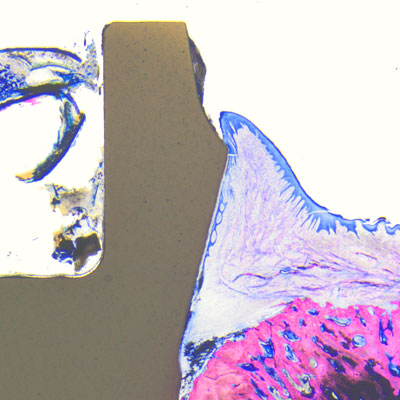

If the Patent™ Implant is placed correctly according to the manufacturer’s surgical protocol (and not inserted too deeply), the interface between the crown margin and the implant table is at the equigingival level and the ferrule with the 3C implant connection at its center is at the supragingival level. Without there being a bacteria-prone subgingival microgap, the peri-implant soft tissues can begin to adhere firmly to the transgingival tulip in the form of a cuff shortly after insertion, largely free of irritation and undisturbed by bacterial pathogens. Because of this so-called “early sealing” of the mucosa to the transgingival implant portion, the risk of subgingival cement residues or glass fiber components (as a result of the intraoral cementation process) is virtually non-existent.to them.

Thanks to its soft-tissue-level design, among other things, the Patent™ Implants does not incorporate a subgingival microgap susceptible to the infiltration and accumulation of bacterial pathogens, which would promote the development of peri-implant inflammation and marginal bone loss. As a result, the stability and the health of the peri-implant hard soft and hard tissues is maintained over the long term. This has been scientifically proved: Becker et al. and Brüll et al. observed an increase in keratinized gingiva around inserted Patent™ Implants in their 2- and 3-year clinical studies after the respective study periods.2, 3 In the long-term follow-up study by Becker et al. Patent™ Implants placed in patients with average health profiles showed healthy soft-tissue conditions with mucosal recession of <1 mm, stable bone and soft-tissue levels and no signs of periimplantitis—even after almost a decade of wear.4 Also, as part of a retrospective long-term study, Dr. Sofia Karapataki observed over 90 Patent™ Implants inserted in a cohort of compromised patients for a functional period of up to 12 years and she found that none of the implants investigated showed signs of peri-implantitis.5 to them.